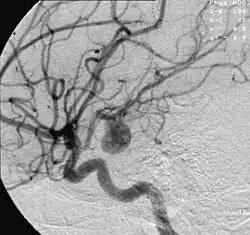

![]() Angiografía de un aneurisma en una arteria cerebral. | ||